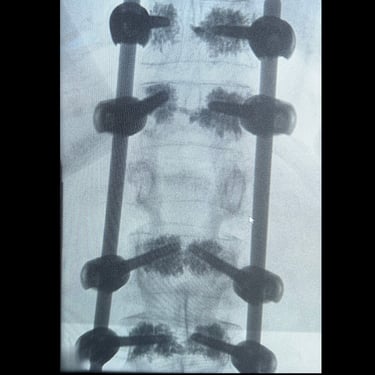

🧠 Fractura Lumbar – Fijación Transpedicular (FTp).

La fractura lumbar inestable se trata frecuentemente con fijación transpedicular (FTp), utilizando tornillos y barras para estabilizar la columna y proteger estructuras neurológicas. Esta técnica favorece la consolidación ósea, permite movilidad temprana y reduce riesgos, siendo una opción segura y efectiva para fracturas lumbares complejas.

🧠 Fractura vertebral lumbar – Artrodesis con tornillos transpediculares (FTP).

La fractura vertebral lumbar puede causar inestabilidad y dolor severo. La artrodesis con tornillos transpediculares es una técnica quirúrgica eficaz que estabiliza la columna, protege las raíces nerviosas y mejora la recuperación funcional del paciente.